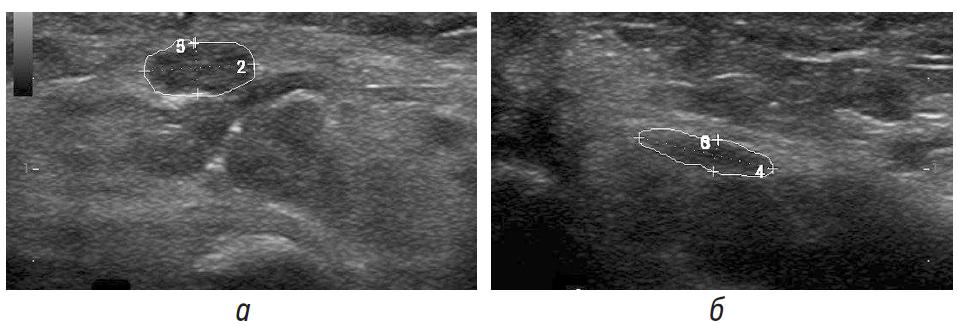

Со слов пациентки, жалобы на выраженную боль в правой кисти отметила после полученной травмы правого лучезапястного сустава в результате резкого рывка при опоре на поручень во время резкого торможения маршрутного такси на светофоре. Она неоднократно проходила стационарное и амбулаторное лечение с незначительным положительным эффектом. Через 4 мес после травмы выполнялась операция: пластика полулунно-ладьевидной связки аутотрансплантантом из сухожилия лучевого сгибателя правой кисти. Болевой синдром отмечался на протяжении около года. При выполнении ЭНМГ данных за поражение моторных и сенсорных волокон срединного и локтевого нервов выявлено не было. ЭНМГ признаки наличия анастомоза Мартина–Грубера 3-го типа. Однако при выполнении УЗИ правого запястного канала на уровне лучезапястного сустава определялась зона посттравматических рубцово-спаечных изменений мягких тканей, через которую проходил правый срединный нерв. В карпальном канале диаметр нервного ствола был неравномерный — в проксимальных отделах размеры нерва 2,8 × 6,0 мм, площадь поперечного сечения 16 мм2, в дистальной части — 17 × 75 мм, площадь поперечного сечения 11 мм2, внутренняя дифференцированная структура гипоэхогенная, контур эпиневрия четкий, непрерывный (рис. 2).

Рис. 2. а — УЗИ срединного нерва на уровне входа в запястный канал (поперечное сканирование); б — УЗИ правого срединного нерва при поперечном сканировании срединного нерва в карпальном канале

Особенностью данного клинического случая является диссоциация между полученными результатами ЭНМГ и УЗИ срединного нерва, которая могла свидетельствовать о наличии других вариантов строения нервного ствола и иннервации целевых мышц тенера кисти [14].